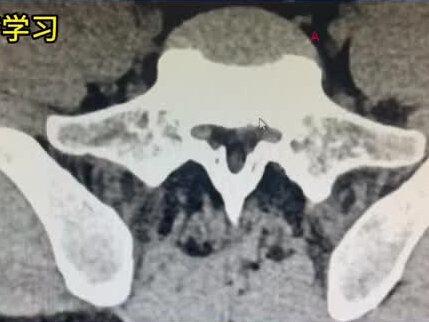

椎管狭窄是一个大的概念,椎管狭窄当中有分三种情况,中央管狭窄、侧腋窝狭窄、椎间控狭窄,对你来说呢,就是一个典型的侧阴窝狭窄,这两个层面就是幺四五走位,前边这是椎间盘,这是椎体 后边的这椎管夜膜囊没有明显受压,中央管的面积比较大,没有狭窄,但是呢,你左侧的侧阴窝开始狭窄了,我们看这个地方,这有个小凹,这是右侧的侧阴窝,因为看到里边有个小白点,这个点就是右侧的腰部是那么同样这边呢,这是侧阴窝, 但是你看不到那个小白点了,对吧?看到这一片偏高密度的,在 ct 上我们称为密度,这个地方实际上是一小块椎间盘突出,椎间盘突出以后,堵住这个侧心窝了,那么这个侧心窝就狭窄了,这个神经啊,就堵在里边去了, 就影响到腰部神经根的血运,影响他的神经传导了,那么就会出现间歇性波形。有些人呢,站不能久站,走不能走远,走了以后呢,出现单侧下肢,比如说你是左下肢酸困沉乏,有些疼, 到这里呢,他就出现麻。所以你这个病诊断大的概念呢,叫椎管狭窄,更精确一点呢,就是侧经络狭窄。 再像这种,如果保住治疗效果不好的,那就要做一个微创手术。怎么做微创手术呢?这是黄领带,看到没有?我们要从这个黄领带这个地方打一个小空进来以后,跟这一块轻微的磨一磨,然后把侧影窝打开,把这个地方清理干净,这个神经就不受压了,你的症状就缓解了。